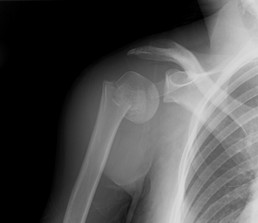

In a moment of inattention last week, I lost my balance while backing a large V-twin out the shop door. Instead of letting out a high-pitched scream and letting the bike fall, my reflex was to struggle to keep the bike upright. The bike weighs 800 lbs. I weigh 150. Someone had to win, someone had to lose. The bike headed for the ground, and most of the rotator cuff muscles in my right shoulder went there with it. As a bonus, they fractured the top of my right humerus on the way. Of course, I danced around for a few minutes, thought I was going to puke, and did the John Wayne thing: I forgot it and got back to work. After I closed for the night, about 9 hours later, I hopped on the XS2 and rode about 15 miles to the hospital, just to make sure I was OK. I’m OK, but my shoulder is a mess. The Doctor says it will be THREE MONTHS before I ride again. This, my friend, is really really bad news.